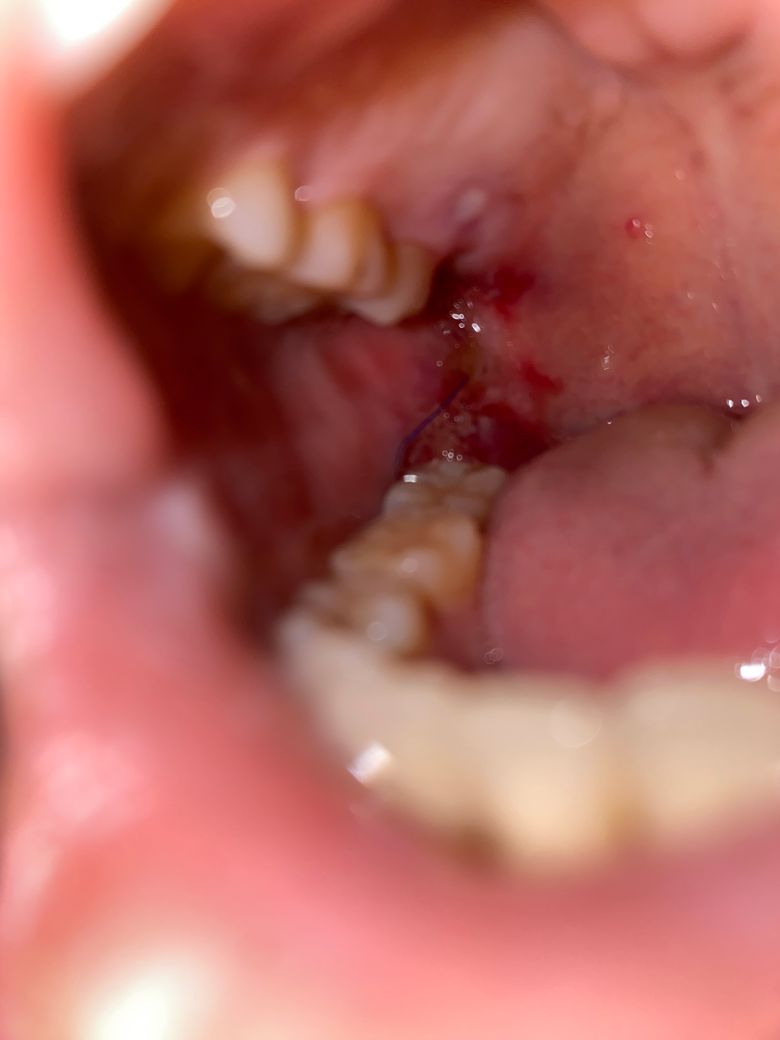

사랑니 발치 후 잘 회복되고 있는 걸까요? 그리고 실밥 길게 봉합해주시나요?

어제 오전 9시에 매복 사랑니 발치를 하였는데요,

사진처럼 하얗게 부분부분 있는 것은 아무느라 있는게 맞을까요?

그리고 실밥을 당일에 확인했을 때도 꽤 길게 되어있기는 한데 매복 치아 봉합도 ➰ 이렇게 길고 느슨하게 하는 경우도 있나 걱정이 되서요ㅠㅠ

우선 실밥 풀린 것 같지는 않지만 내일 발치한 대학병원 가볼까 생각중입니다

사진상으로 보면 잘 아물고 잇는거 같습니다. 그리고 실밥은 음식물이 들어가지 말고 묶어 놓는거라서 느슨해도 크게 문제가 되진 않습니다.